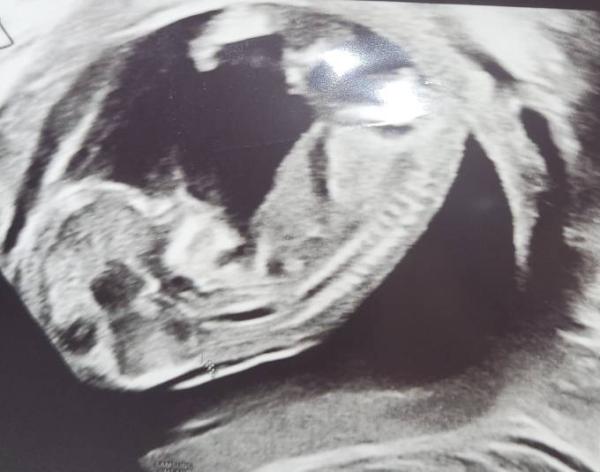

Hey ich war heute bei der frühen feindiagnostik was würdet ihr sagen was es wird ?:)